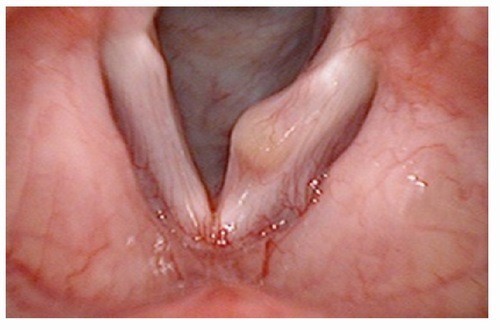

1.3. U nang dây thanh:

- Bề mặt của dây thanh quản được phủ bởi biểu mô có tuyến nhầy và được sắp xếp tạo ra các nếp gấp. Chính các nếp gấp này khiến cho dây thanh dễ rung hơn và tạo thành giọng nói. Âm sắc của tiếng nói, tiếng hát khác nhau giữa từng người là phụ thuộc vào sự đa dạng của các cấu trúc này. Vì có kết cấu là các nếp gấp, đôi khi một trong những tuyến tiết nhầy trên lớp biểu mô này sẽ không thoát được dịch tiết ra ngoài. Hệ quả là sự tích tụ chất nhầy có vỏ bọc sẽ tạo thành u nang dây thanh.

Nguyên nhân:

U nang dây thanh có thể xảy ra thứ phát do lạm dụng giọng nói quá nhiều hoặc có thể là do lớp biểu mô bị mắc kẹt trong các nếp gấp. Bên cạnh đó, các u nang tích trữ chất nhầy có thể xảy ra tự phát hoặc có thể liên quan đến việc vệ sinh giọng nói kém. Khi sự tích tụ ngày càng nhiều, kích thước u nang tăng lên, chúng có thể bắt đầu gây ảnh hưởng đáng kể đến vùng rung của dây thanh âm và biểu hiện qua sự thay đổi giọng nói.

Ngoài ra, một số nghiên cứu cho thấy Streptococcus pseudopneumoniae và, có thể, Pseudomonas, đóng một phần vai trò trong các nguyên nhân của những tổn thương nếp gấp trên dây thanh có bản chất lành tính, chẳng hạn như u nang, nốt sần, polyp và phù nề. Tuy nhiên, các chủng vi sinh vật này lại không dễ dàng được tìm thấy thông qua xét nghiệm các mẫu nước bọt, dịch phết cổ họng hay các bệnh phẩm thông thường trên đường hô hấp.

Hình 4 :U nang dây thanh